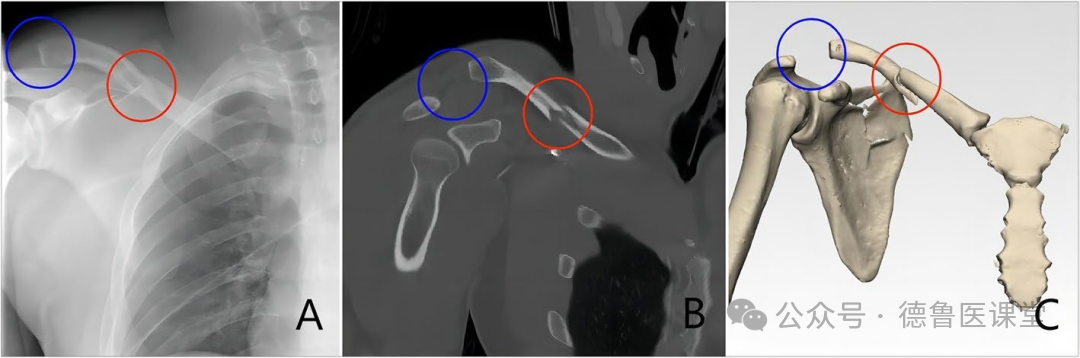

小编就遇到过1例,病人锁骨中段骨折,合并肩峰骨折,术前CT、X线均未发现合并同侧肩锁关节脱位,术中观察不够仔细,术后复查拍片见肩锁关节脱位,还好,本病人在诊疗过程中患者发现肾脏早期肿瘤,在手术治疗肾脏肿瘤的同时进行了二次肩锁关节脱位手术,未出现纠纷。

关于同侧锁骨骨折合并肩锁关节损伤时,肩锁关节损伤可能被低估或漏诊的原因的图解说明。(A)当锁骨骨折与肩锁韧带和喙锁韧带完全断裂同时发生时,由于重力及局部肌肉的牵引作用,侧方锁骨可能出现“浮动”并随肩胛骨一起向下移位,导致在X线和CT影像上产生肩锁关节未脱位的假象;(B)在这种情况下,只有在通过内固定使锁骨恢复连续性之后,实际存在的肩锁关节损伤才会显现出来,从而导致“延迟性”的肩锁关节脱位。